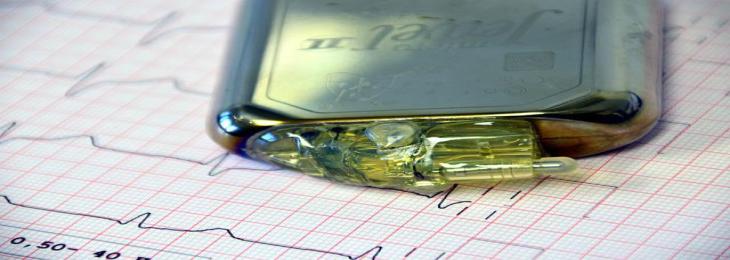

The innovative technique provides results in 10 minutes compared to a standard blood test, which requires at least an hour. A hear...

The tracker includes both ECG and EDA sensors, which were first mentioned in the higher-end Sense, to assist users to monitor their heart health and stress. ...

A combination of a statin, aspirin, and two blood pressure medications has been shown to help reduce the risk of fatal cardiovascular disease (CVD) by more than half....